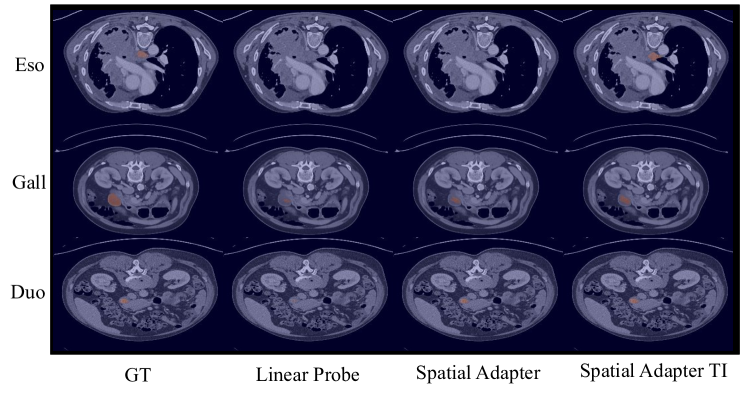

Qualitative evaluation.

In the following, we introduce in Figure 3 a qualitative assessment of the performance of the proposed adapter, using the few-shot setting with . The visualizations show the benefits of incorporating anatomical constraints regarding organ proportion during adaptation (first and second rows). Also, we observe the segmentation improvement of training a small adapter module on top of the backbone for efficient fine-tuning (second and third rows).